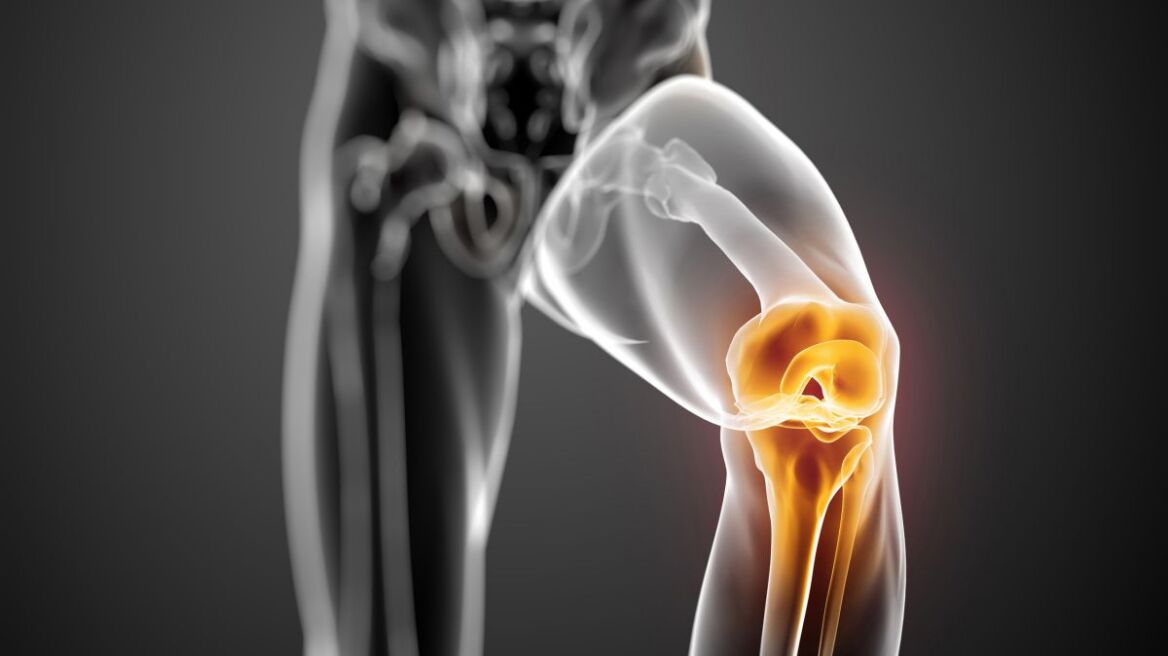

Πρωτοποριακή αρθροσκοπική μέθοδος αποκατάστασης βλαβών αρθρικού χόνδρου στο γόνατο με εμφύτευση αυτόλογων χονδροκυττάρων που καλλιεργήθηκαν στη διάρκεια της επέμβασης, εφαρμόστηκε πρόσφατα (στις 5/9) στη Θεσσαλονίκη σε μία 30χρονη αθλήτρια και σε έναν 45 αθλούμενο, από την ιατρική ομάδα του TheMIS η οποία απαρτίζεται από τους ορθοπαιδικούς χειρουργούς Αριστοτέλη Σιδερίδη, Εμμανουήλ Παπακώστα και Ιωάννη Τερζίδη.

Μέχρι τώρα για να γίνει αποκατάσταση των βλαβών του αρθρικού χόνδρου με μεταμόσχευση αυτόλογων χονδροκυττάρων έπρεπε να γίνει μια επέμβαση προκειμένου να ληφθούν τα χονδροκύτταρα τα οποία στέλνονταν στο εξωτερικό για να απομονωθούν και να πολλαπλασιασθούν σε συνθήκες εργαστηρίου και στη συνέχεια, με δεύτερη χειρουργική επέμβαση γινόταν τοποθέτηση του «μοσχεύματος» για την κάλυψη της βλάβης.

«Με την τεχνική που εφαρμόσαμε εμείς η καλλιέργεια έγινε από βιολόγους που ήρθαν από την Ολλανδία γι αυτό το σκοπό μέσα σε 70 λεπτά, την ώρα του χειρουργείου σε εργαστήριο που είχε στηθεί δίπλα στο χειρουργείο. Ετοιμάστηκε δηλαδή το «μόσχευμα» με τα χονδροκύτταρα του ασθενούς. Αυτά απομονώθηκαν στο φορητό εργαστήριο από το εξειδικευμένο προσωπικό, με πιστοποιημένο και πατενταρισμένο τρόπο, και τοποθετήθηκαν σε ειδική μεμβράνη - φορέα η οποία στη συνέχεια τοποθετήθηκε στην περιοχή της βλάβης. Η όλη επέμβαση διήρκεσε περίπου δύο ώρες και το κόστος ήταν πολύ μικρότερο. Δηλαδή αποκατάσταση της βλάβης του αρθρικού χόνδρου με δύο επεμβάσεις κοστίζει γύρω στις 17.000 ευρώ ενώ με τη νέα τεχνική κοστίζει γύρω στις 3.500-4.000 ευρώ. Έτσι, ο ασθενής εκτός από το ότι αποφεύγει τη δεύτερη επέμβαση επιβαρύνεται λιγότερο οικονομικά, γιατί αυτές οι επεμβάσεις δεν καλύπτονται από τα ασφαλιστικά ταμεία» ανέφερε στο Αθηναϊκό Πρακτορείο Ειδήσεων ο κ. Σιδερίδης.

Η μέθοδος αυτή, όπως εξήγησε ο κ. Σιδερίδης, είναι κατάλληλη για πρόσφατες βλάβες κυρίως για αθλητές που έχασαν τμήμα αρθρικού χόνδρου λόγο τραυματισμού. Οι βλάβες του αρθρικού χόνδρου αποτελούν το προστάδιο της αρθρίτιδας η οποία αντιμετωπίζεται μόνο με μεταλλικό γόνατο.